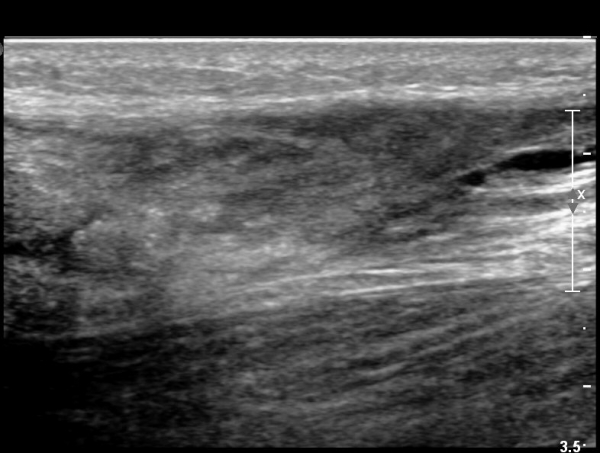

³»Ãø ºñº¹±Ù Á¾´Ü¸é°Ë»ç¿¡¼­ ³»Ãø ¹èº¹±Ù ¸»´ÜºÎ ÆÄ¿­°ú °¡Àڹ̱٠½ÉºÎ¿¡ ¼ö¾×Àú·ù°¡ °üÂûµÊ(»çÁø 1, 2).

¾ÆÅ³·¹½º°Ç Á¾´Ü¸é°Ë»ç¿¡¼­ ¾ÆÅ³·¹½º°Ç ¸»´ÜºÎ¿¡ ¾ÆÅ³·¹½º°ÇÀÇ Àú¿¡ÄÚºÎÁ¾, ±¹¼ÒÀû ¿¬°á¼º ¼Ò½Ç,

¹ß¸ñ°üÀý ÈĹæºÎ¿¡ ¼ö¾×Àú·ù°¡ °üÂûµÊ(»çÁø 3, 4, 5).